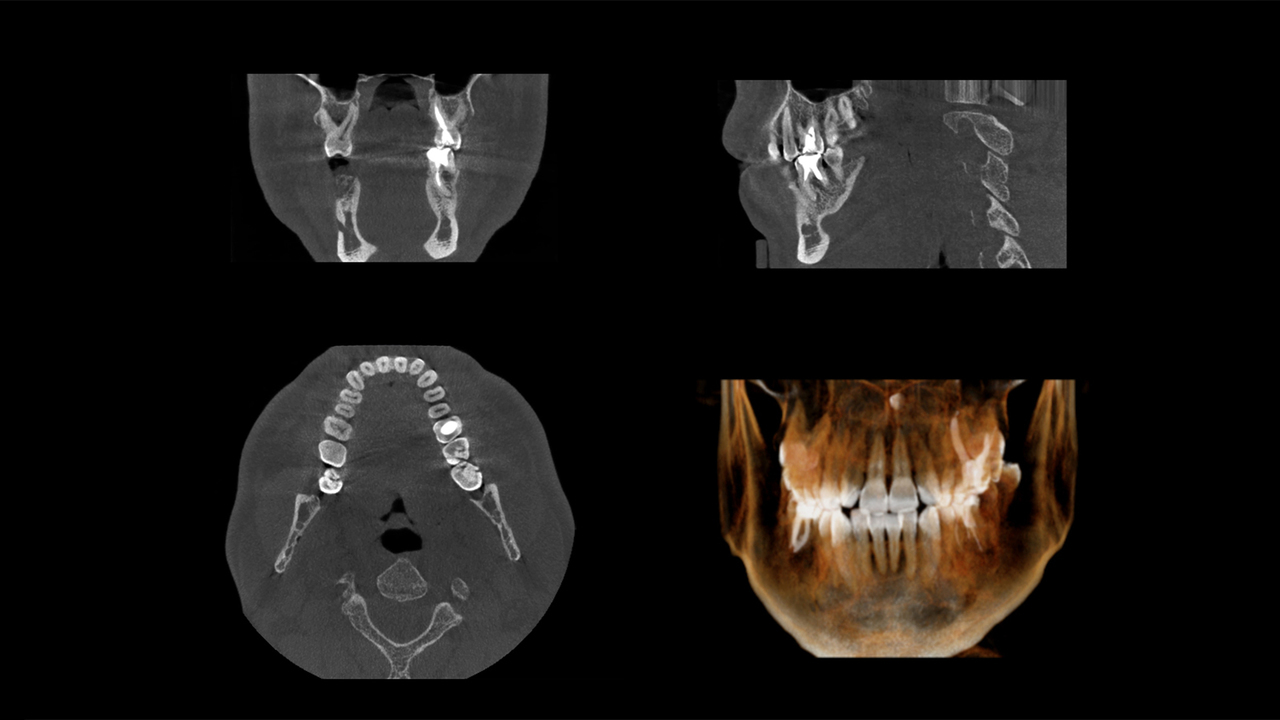

CTとは、コンピューター断層撮影法(Computed Tomography)を行う装置です。撮影データをコンピューターで処理し、三次元のデータで確認できます。

歯科用CTは、歯科の治療に必要な頭頸部の撮影に特化された装置。あごの骨の厚みや骨密度を確認できるほか、歯や神経の位置なども立体的に把握できます。

従来の平面的なレントゲン写真では見えなかった情報を得られるため、より高精度な診査・診断を行うことが可能です。

従来の歯科用X線写真(パノラマレントゲン)は、平面的な画像です。大まかに歯やあごの骨の状態を確認したい場合は問題ありませんが、インプラント治療や親知らずの抜歯など、より精度の高い情報が求められる診断には不十分でした。

しかし歯科用CTであれば、あごの骨の厚みや高さ、歯の根の先端からあごの骨の中の神経血管の管までの距離など、より詳細な情報を立体的に得られます。

歯科用CTは、従来のレントゲン写真(パノラマレントゲン)に比べて多くの情報を得られます。3Dで360度あらゆる角度から歯やあごの骨の状態などを確認できるため、インプラントをはじめとした外科治療などにおいて、より高い安全性や治療精度の向上につながっているのです。